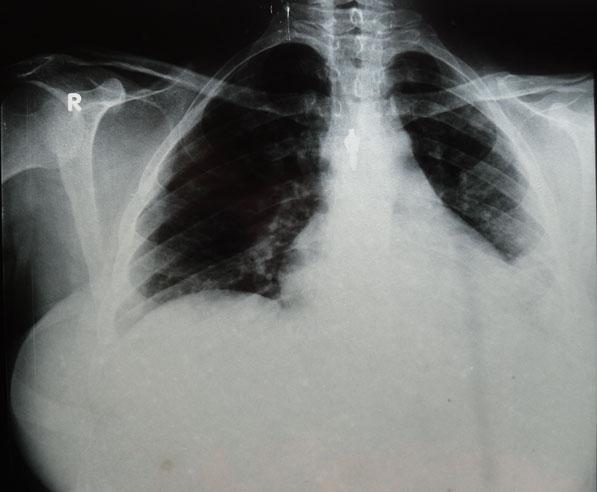

Chronological Photo-sequence

of the case progression

-On presentation: